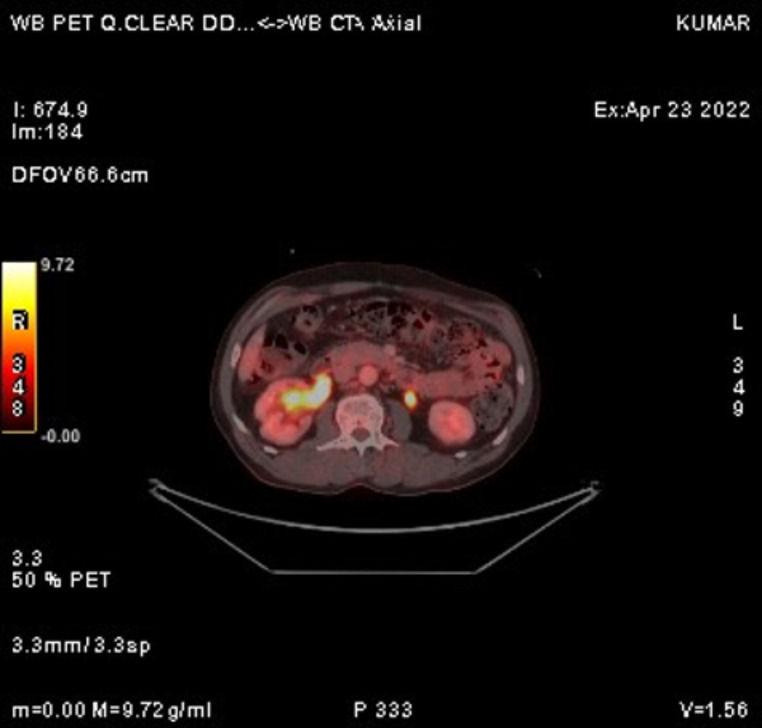

The recent FDG PET/CT scan revealed significant disease progression compared to the previous scan. Findings included the interval development of multiple hypermetabolic soft tissue lesions in the perirectal bed, indicating recurrence. Additionally, there was an increase in size and metabolic activity of several new bilateral lung nodules, newly enlarged mediastinal lymph nodes (Fig. 5), and hypermetabolic sclerotic lesions at previously affected skeletal sites (Fig. 6), all consistent with metastasis.

Fig. 6.

FDG PET CT scan showing a hypermetabolic lesion in the mandible, consistent with metastatic involvement